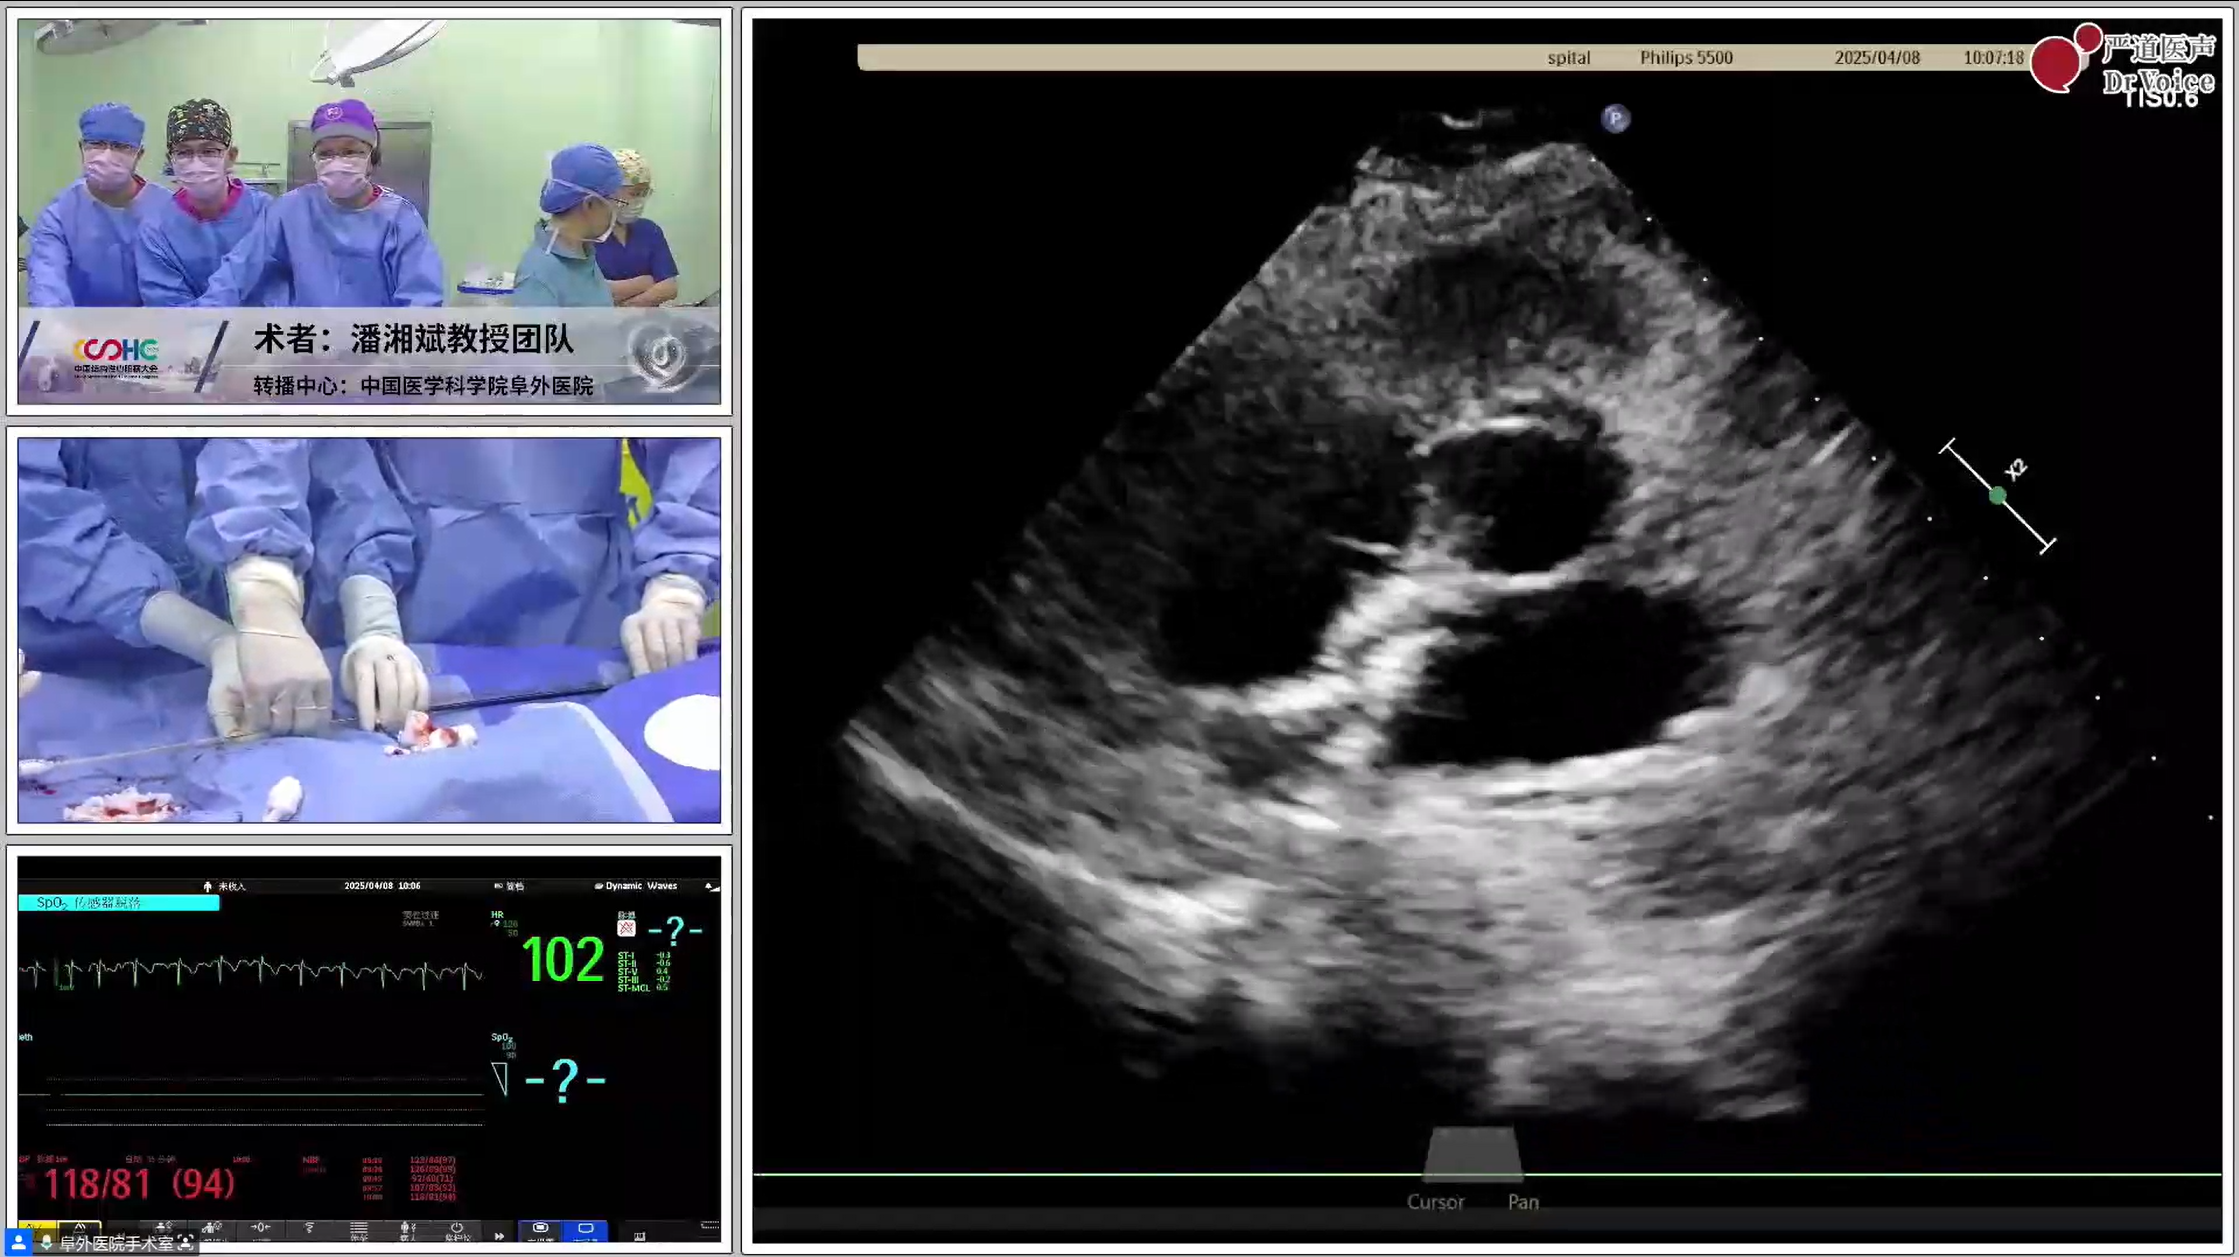

左:第一例手术录播、右:第二例手术直播

第一例患者较年轻,有脑梗史,反复头痛数年,经食道发泡试验阳性,提示存在PFO。第二例患者39岁,偏头痛10余年,头颅核磁提示多发缺血灶,食道超声证实PFO,宽约2.4 mm、长约8 mm。两例患者均具备封堵指征,结合患者意愿,经术前充分检查后拟行单纯TTE引导下可降解PFO封堵,分别植入对称型24 mm*24 mm可降解PFO封堵器、对称型24 mm*24 mm可降解PFO封堵器。

为减少大鞘在心房内停留时间,可提前装载封堵器。两例手术均在单纯超声指导下开展,第二例患者术中通过导管配合超声导丝法顺利过隔,第一例患者经导管导丝探查法尝试过隔未果后,改用鞘管配合导丝法。术中所采用的PannaWire超声专用导丝为两例手术的新利器,其头端呈梭型,超声很容易探测,具有较佳的指向性,既降低了过隔难度,又提升了操作安全性。对于第一例患者,经超声确认导丝头端位于卵圆窝附近后,保持鞘管头端垂直指向房间隔方向缓慢推送,待导丝头端影像消失即提示鞘管已成功贴靠卵圆窝,后在其支撑下,导丝顺利过隔,建立股静脉至左心房的导丝轨道。

完成导丝轨道建立后,置入输送鞘。封堵器经鞘顺利送入左房后,在超声引导下先释放左盘面,通过牵拉成型线使其由“灯笼状”变为“盘状”,再回撤钢缆,使左盘紧贴房间隔。待右盘面释放后牵拉成型线,若超声下观察到右盘随房间隔摆动,且双盘贴合于间隔、形态合适,即开始锁定。成型锁定后,超声下双盘面紧紧扣合在房间隔两侧,形态良好,且轻轻牵拉钢缆,双盘相对位置保持不变,依然紧贴合房间隔,判定锁定成功。